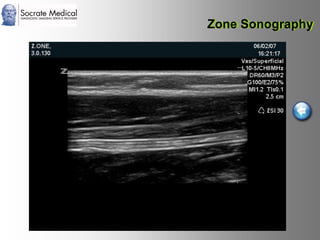

Il documento presenta la tecnologia della zone sonography, che promette una rivoluzione nel campo degli ultrasuoni, superando i limiti dei sistemi tradizionali grazie a metodi di acquisizione dati più veloci e una gestione delle informazioni migliorata. Questa tecnologia consente una maggiore definizione dell'immagine, una riduzione degli artefatti e un'ottimizzazione del processo diagnostico, con vantaggi in termini di tempo e costi. Inoltre, il channel domain processing e la zone speed technology offrono applicazioni avanzate e miglioramenti nella sicurezza diagnostica.